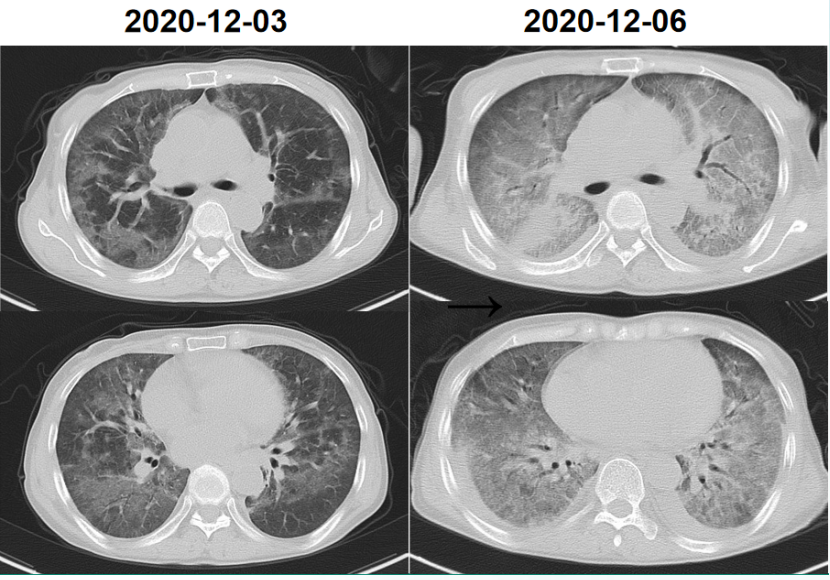

本例患者在治疗过程中拒绝服用SMZ(肝功能欠佳),单用卡泊芬净+激素治疗,后加用SMZ治疗,氧合较稳定。出院后单用SMZ,效果较好(图9)。本例患者因个人原因初始治疗并未使用SMZ,最终预后及疗效较佳,治疗过程也侧面反映了抗感染强度可能并不是疾病治疗最重要的因素,治疗初期抑制肺部损伤所致炎症反应也非常关键。

图片

9  患者治疗过程中胸部CT变化情况